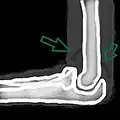

| Joint effusion | |

| A traumatic right knee effusion. Note the swelling lateral to the kneecap as marked by the arrow. | |